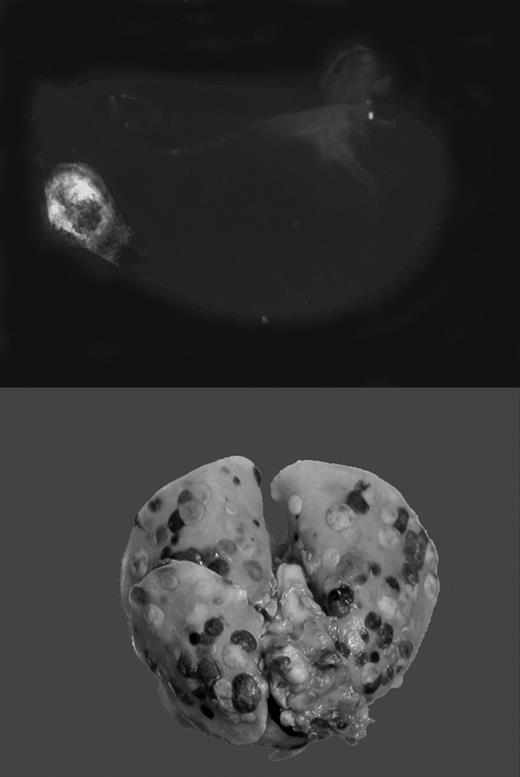

Gαq deficiency dramatically diminishes the metastatic potential of circulating tumor cells. See the complete figure in the article beginning on page 178.

Tumor cells travel through blood or lymphatic vessels to secondary organs, where they exit the vascular compartment to form metastases. This route of tumor dissemination through the bloodstream has been termed hematogenous metastasis. The level of tumor-associated procoagulant activity correlates directly with metastatic potential, and forced expression of the initiator of blood coagulation, tissue factor (TF), is sufficient to confer metastatic potential onto tumor cells.1 In animal models, metastasis can be effectively suppressed by genetic disruption or pharmacologic inhibition of the coagulation system or platelet activity. Using genetically altered mice lacking fibrinogen, Palumbo and colleagues previously demonstrated that absence of fibrinogen markedly reduces the formation of pulmonary and lymph node metastases, without affecting growth of the primary tumor.2 Recent work by Camerer and colleagues3 confirms this finding, and, in addition, showed that platelets are also necessary for successful hematogenous metastasis. Importantly, attenuating platelet responsiveness to thrombin suppressed metastasis to a similar extent as the complete absence of platelets, or the lack of fibrinogen. Together, these studies clearly established that metastasis of circulating tumor cells requires TF-initiated coagulation on the surface of tumor cells, which promotes thrombin generation, fibrin formation, and platelet aggregation. However, it remained obscure how this chain of events translates into an enhancement of metastasis.FIG1